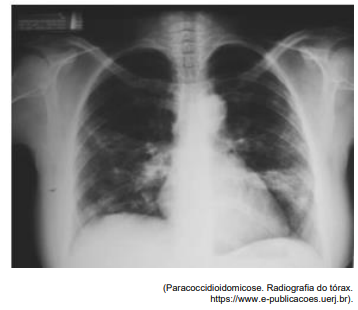

Analise a radiografia abaixo para responder à questão.

A radiografia demonstra, notadamente,